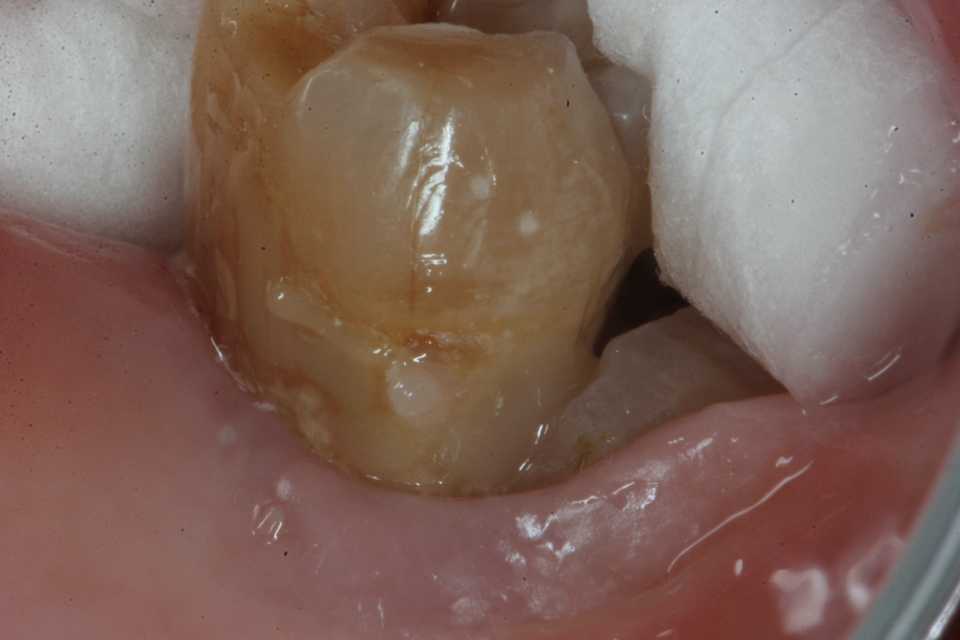

ストリップスを使わない隣接面CR(ダイレ… 2025.11.03